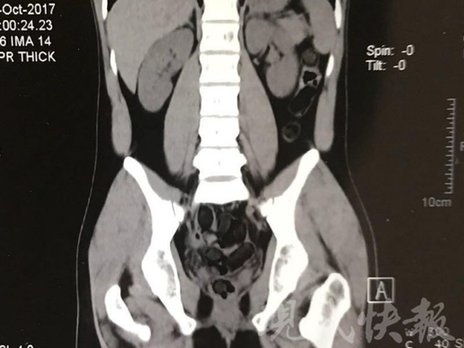

小伙體內(nèi)藏毒300余克 CT掃描圖密密麻麻

由于毒品在體內(nèi)一旦泄露有可能致命,警方第一時(shí)間將阿永帶到醫(yī)院進(jìn)行檢查。CT 掃描的結(jié)果顯示,阿永體內(nèi)布滿了密密麻麻的白色圓柱狀固體,就像一粒粒的蠶蛹。在南京市公安局鼓樓分局二板橋派出所,阿永分四次排出了毒品,毛重369.99克。經(jīng)訊問,阿永交代了自己全部的犯罪事實(shí)。目前,阿永已被刑事拘留。